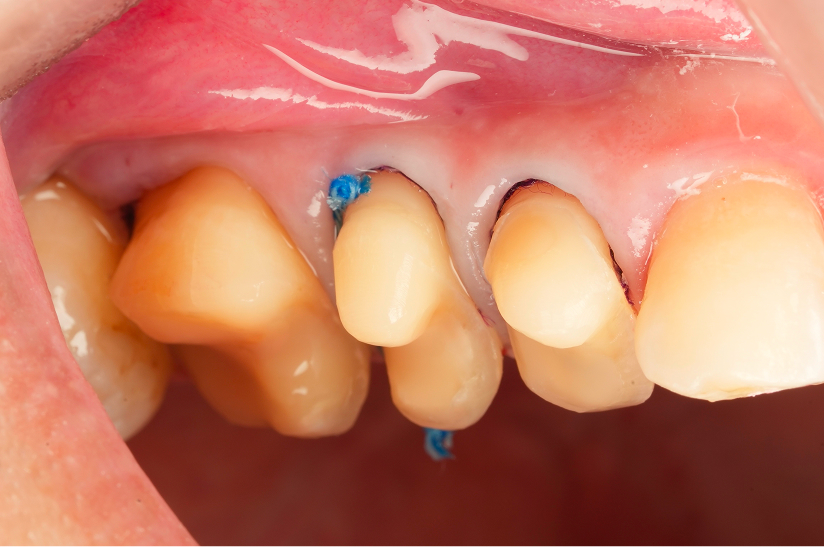

象牙質の汚染保護や接着力を高めるために

ひと工夫して仕上げた症例

Before

After

主訴

虫歯の治療をしたい

治療内容

Immediate dentin sealing(う蝕除去後の象牙質コーティング)、セラミックアンレー

治療費用

137,500

治療の

リスク

経年的に材質の破折、脱離の可能性があります。